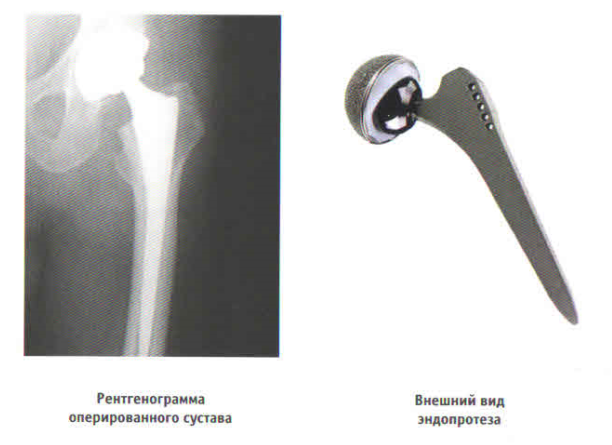

Во время операции все деформированные участки хряща аккуратно срезаются и на их место устанавливаются искусственные части, которые точно повторяют форму здоровых. Между металлическими частями помещаются полимерные вкладыши, выполняющую амортизационную функцию и улучшающие скольжение металлических поверхностей.

Как правило, мы используем особо прочные металлические сплавы, например кобальт-хром-молибден. Существует еще и металлокерамические импланты, они в разы долговечнее металлических, и значительно дороже.